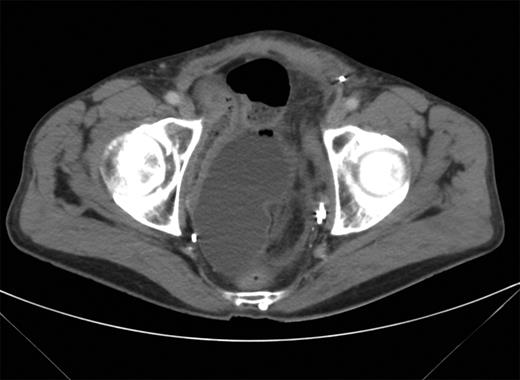

A 71-year-old male had undergone a radical cystectomy and orthotopic neobladder formation 5 years previously, and was self-catheterising. He presented to the emergency department with a 24-h history of abdominal pain and distension. There was associated nausea and a reported decrease in urine production. Examination revealed a distended abdomen with some lower abdominal tenderness but no evidence of peritonism. Bowel sounds were absent. Relevant blood analysis revealed creatinine 354 µmol/l, WCC 15.9 × 109/l and CRP > 380. An abdominal X-ray revealed dilated small bowel loops, and a CT showed moderate volume ascites and distal small bowel obstruction with the transition being a thickened small bowel loop lying next to the neobladder (Fig. 1).

CT scan showing transition point of dilated bowel lying adjacent to the neobladder.